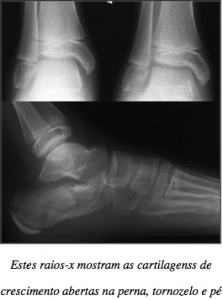

View Raio X De Pe Wallpapers. Contact raio x df on messenger. Objetivos • apresentar o exame de raio x e as suas etapas;